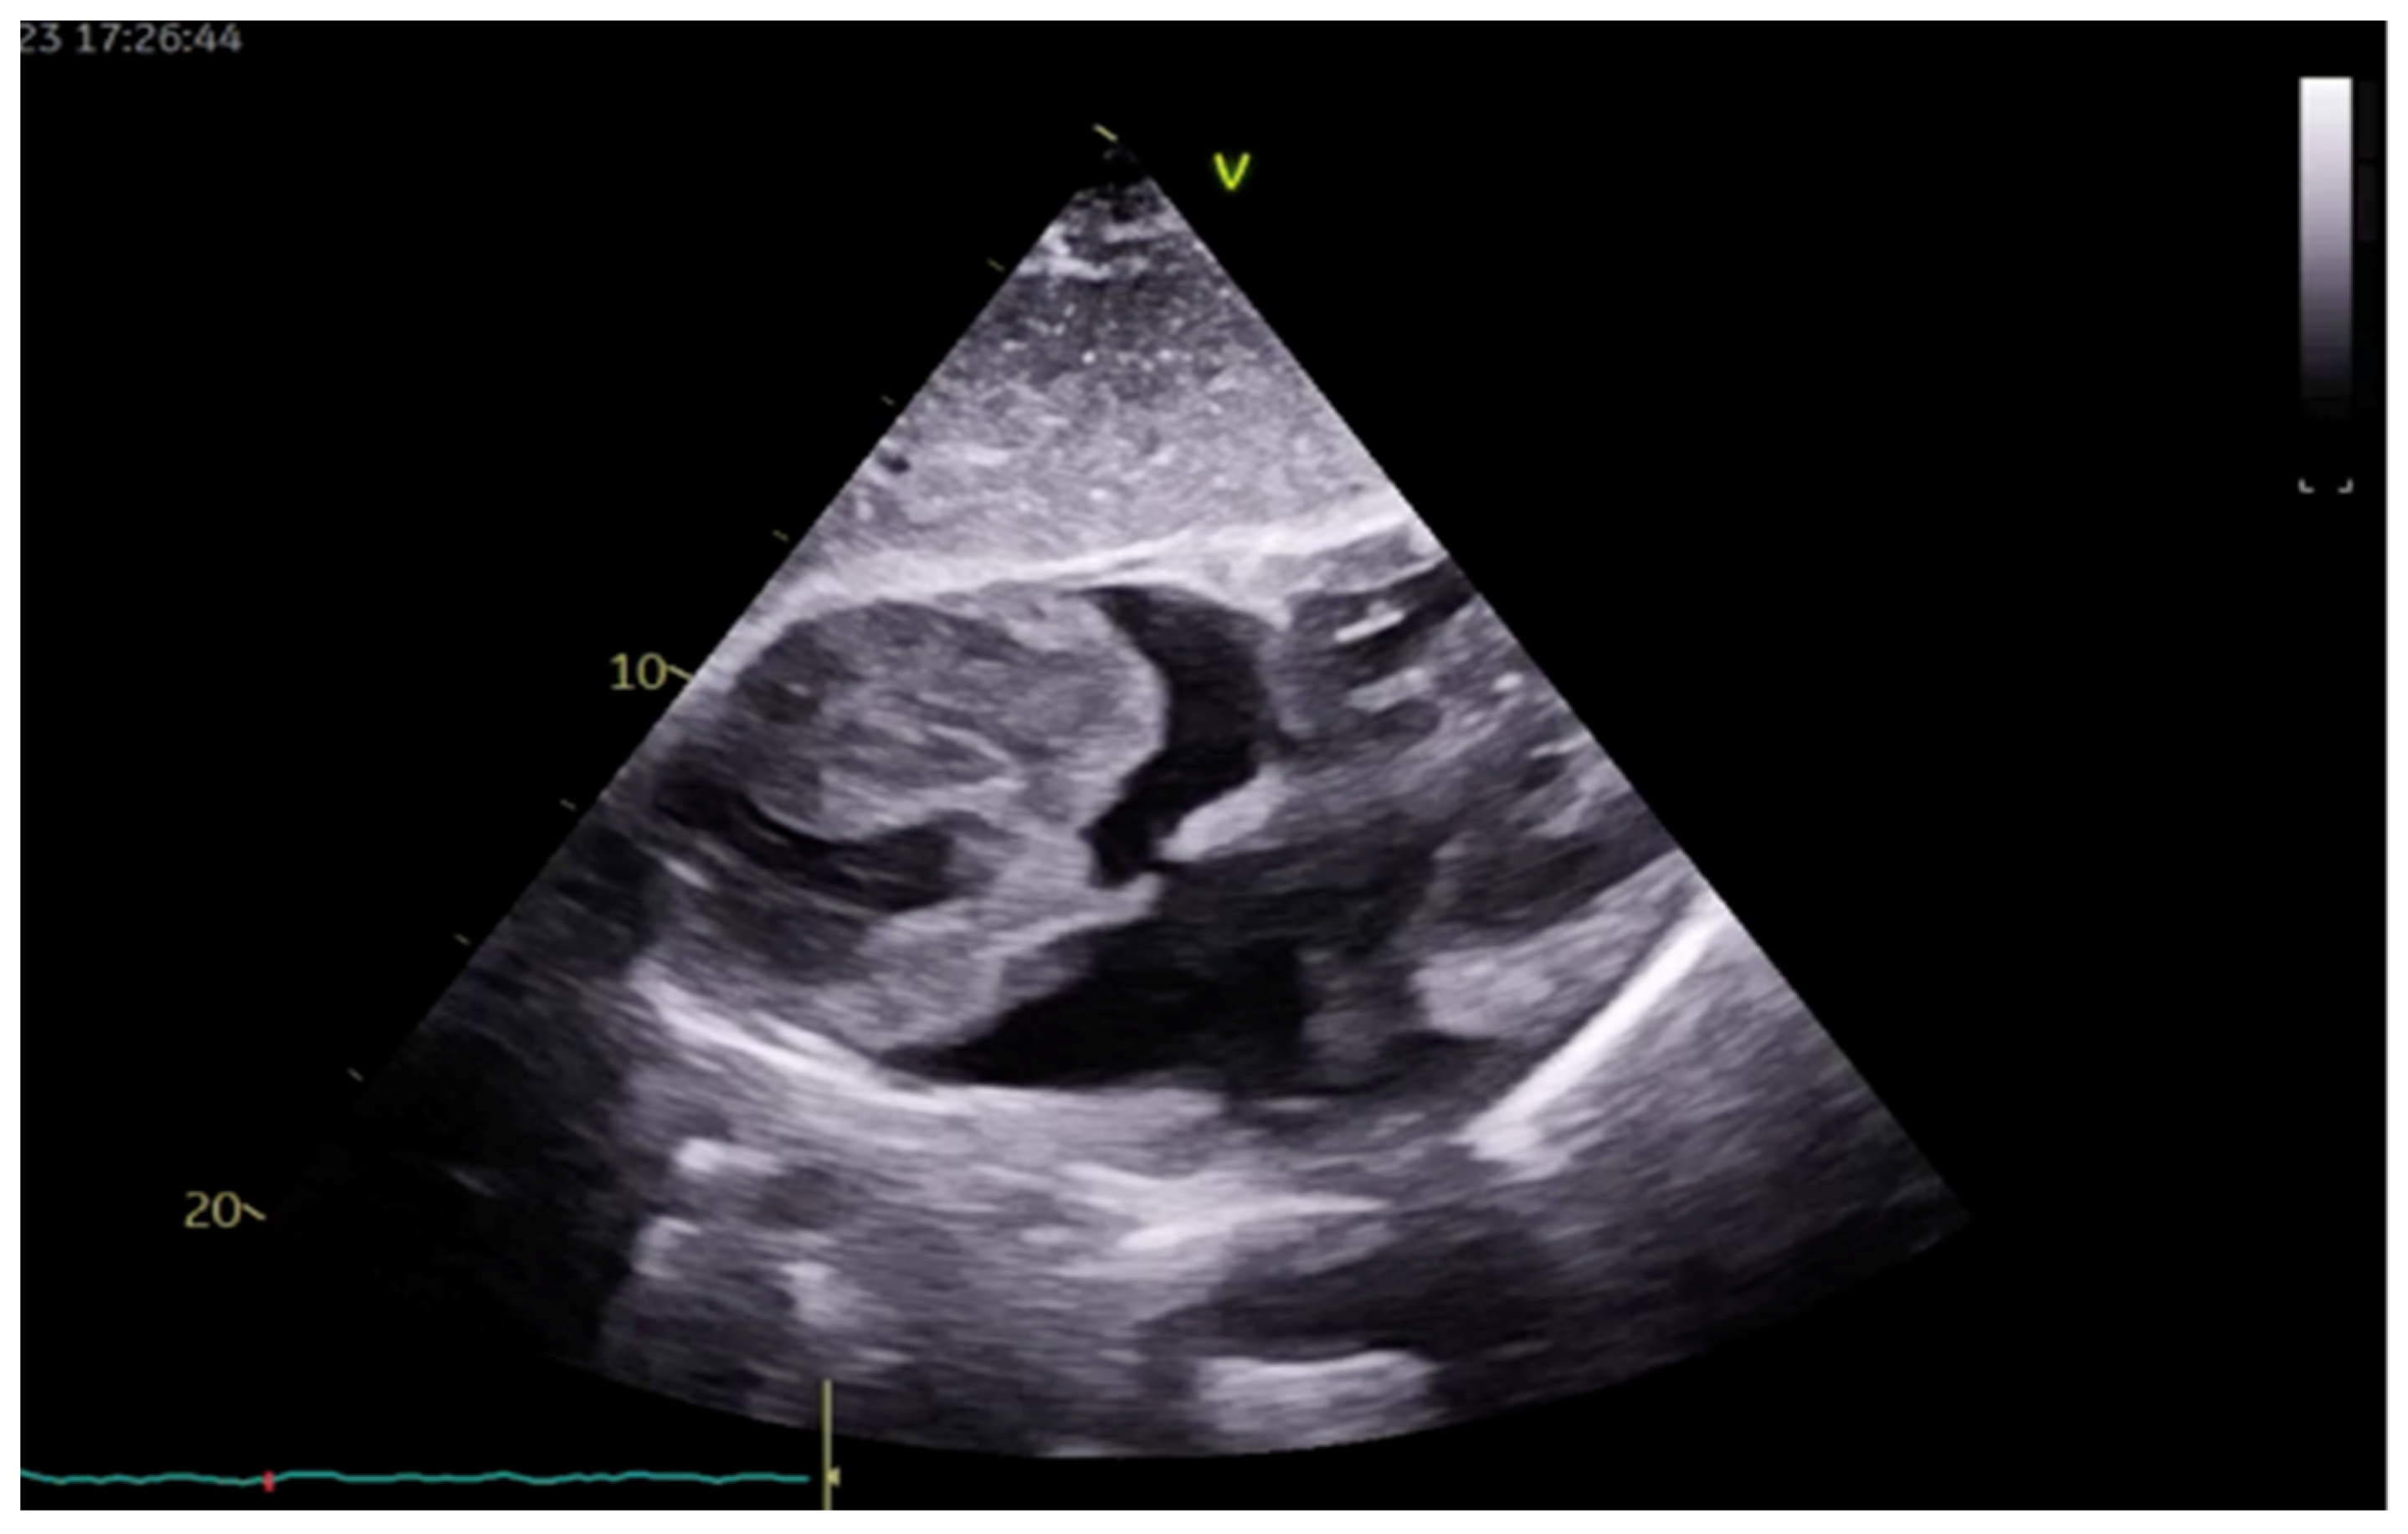

2. Case Presentation